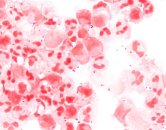

Annual cases of invasive meningococcal disease, a rare but dangerous bacterial infection, have hit the highest level seen in Canada in more than a decade. This rapidly-progressing illness can cause meningitis, sepsis or even death, and children and young adults often bear the brunt.